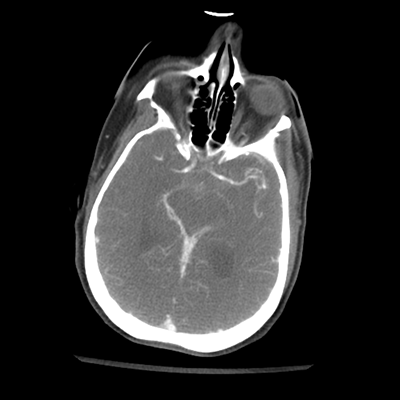

NCHCT

In terms of her neuroimaging, it's clearly abnormal. With the non-contrast head CT, we can see an acute SAH, with blood in the basal cisterns and Sylvian fissures, with some trace blood in the ventricles. The ventricles generally don't look too large, but actually, the temporal horns and atria are visible and larger. So, there's definitely ventriculomegaly that, in combination with her clinical exam, suggests hydrocephalus.

With the CTA of her head/neck, we can sort of see some atherosclerosis (though the images aren't windowed well for this). Importantly, though, we can see a rounded abnormality around the tip of the basilar/left PCA. This is an aneurysm! This helps put things together. This patient had an aneurysmal rupture leading to SAH and hydrocephalus, causing her loss of consciousness. While her leg extensor movements could be seizures, they're probably actually posturing movements, secondary to intracranial hypertension in the setting of her hydrocephalus.